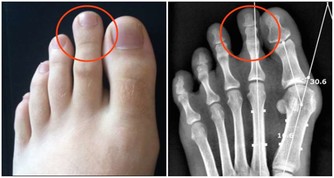

關節僵硬:它們最怕5個字

關節是骨骼之間的連接點,一旦關節出了問題,人的行動力就會受限,久之人就垮了。

1、怕老:隨著年齡的增長,人體軟骨營養缺乏,骨骼中的無機物增多,骨骼彈力與韌性減低,易導致關節軟骨和骨退行性病變。

2、怕胖:體重增加,下肢關節承重的壓力也會增加,引起體位、步態變化,改變關節的生物力學,發生膝內翻或膝外翻,也就是常說的“O”形腿或“X”形腿。

3、怕傷:在運動、出行的過程中,如果出現急性外傷,一定要及時去醫院治療,以免留下後遺症。

不及時治療或充分休息,容易留下病根,比如“習慣性崴腳”。

4、怕勤:關節用得太狠,容易導致機械磨損,破壞軟骨。

頻繁爬山、爬樓等是非常傷害關節的。建議大家平時通過慢跑、游泳鍛煉,既不損傷關節又能鍛煉。

5、怕冷:關節受涼會引起疼痛,易導致關節僵硬。